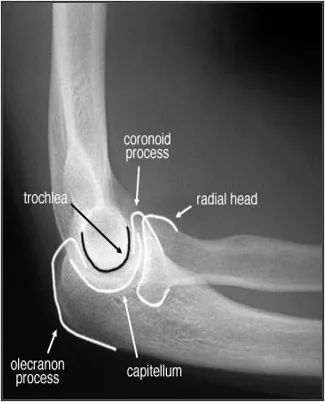

length—长度描述x线片的逻辑顺序骨化中心,骨骺线:注意小儿生长板